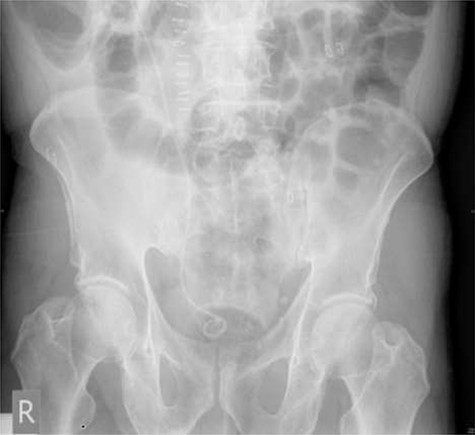

Seven months after the patient’s initial presentation, they underwent a laparoscopic right hemicolectomy; intra-operatively, a 6Ch/24 cm stent was inserted into the right ureter by the colorectal surgeon who had good experience of ureteric stent placement. The position of the stent was confirmed with cystoscopy and retrograde pyeloureterogram (Fig. 2).

Retrograde pyeloureterogram confirming position of right ureteric stent.